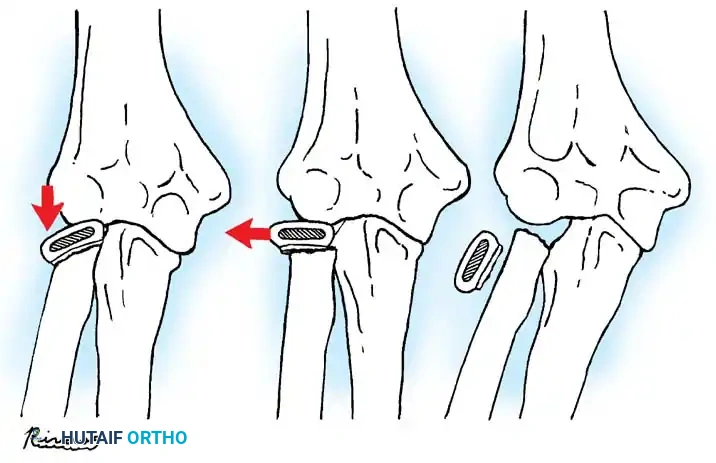

Fractures can present as angulated, translocated (shifted), or totally displaced. In the context of an elbow dislocation, the proximal fragment may become loose within the joint space or trapped, acting as a mechanical block to reduction.

Fig. 33-40 Examples of angulation, translocation, and total displacement of radial neck fractures.